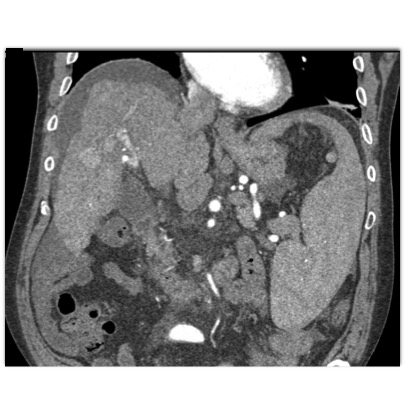

In this patient with Hepatitis C the best diagnosis is?

regenerating nodule

hepatoma

AVM of the liver

hemangioma